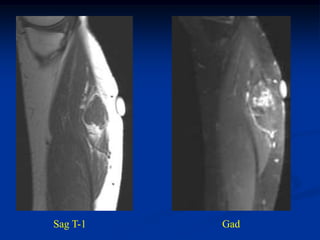

Case #297

phlebolith

6 year female

hemangioma forearm

Case #297.1                    Hemangioma forearm

Cor T-1                          Gad

18 year old female with forearm mass for years

Axial T-1

Axial Gad

Case #297.2     Hemangioma forearm

46 yr male with

tender soft mass

forearm for years

Cor T-1   T-2   Gad

Sag T-1   T-2   Gad

Axial T-1         T-2

Gad

Case #297 phlebolith 6 year female hemangioma forearm

• 307.

Case #297.1 Hemangioma forearm Cor T-1 Gad 18 year old female with forearm mass for years

• 308.

• 309.

Case #297.2 Hemangioma forearm 46 yr male with tender soft mass forearm for years

• 310.

• 311.

• 312.

Axial T-1 T-2 Gad